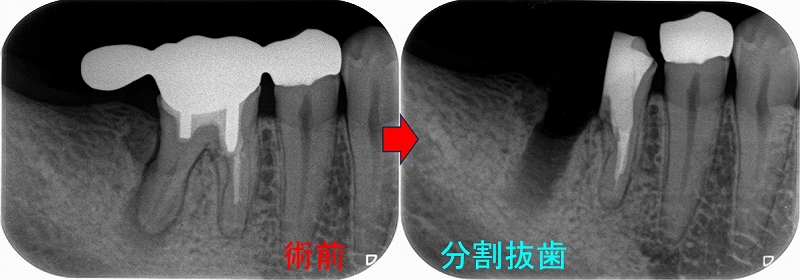

歯牙移植とヘミセクションから10年

先日昔治療させてもらった患者さんが詰め物が取れたということで来院されました。

この部位は

以前、延長ブリッジが入っていた歯

ふと、最近延長ブリッジ見なくなったなと思います。

(昔からあまりやらない方が良い治療だとは思っていましたが)

特に問題無かった歯なので、このままにしておいたのですが、

5年後

遠心根に透過像が出てきており、歯茎からは膿が出てきていました。

日本の根管治療の約6割には問題があるというはあながち間違いではないと思います。

とりあえず根管治療をして治すことにしましたが、

近心根にはパフォーレーション 手付かずの遠心根には破折線が見られ、

患者さんにどうします!?遠心根はまず残せない、近心根は残すことが出来るがパフォーレーションの位置的に長く持たない可能性がある。

不思議なんですが、遠心根は根管治療していないにも関わらず折れてきている。

イメージ的に根管治療を行い中を削って歯を弱体化させている近心根が折れるならまだ分かるのですが・・・

患者さんと話し合い、近心根はヘミセクションをして残す 遠心根は抜歯

右下7の所には親知らずの移植と計画をしました。

この後遠心根抜歯

口腔外科で移植をしてもらい、移植歯の根管治療を行い

ある程度咬めるように治させてもらいました。

今年になり患者さんが詰め物が外れたとのことで来院

10年経過して、そこまで悪い感じはありません。

患者さんにも「先生にそんなに持たないかもしれないよと言われていましたが10年持っています。意外と持つものですね!」と言われましたが、

ホント最初の延長ブリッジの方がかなり良い条件でしたが、折れてしまった。

パフォレーション+分割抜歯、移植した歯という条件の悪いケースで10年経過している。。。

たぶん、私がそんなに持たないかも!?と言った事でかばって咬むようにしているのが

今の状況を作っていると思いますが、ホント術者がどんなに頑張っても咬む力(歯ぎしり含め)で歯は必ず悪くなってきてしまいます。

こういうケースを見ると、患者さんの協力なしで歯を長く持たせることは難しいと感じます。

今回のケースは詰め物のやり替えだけ行えば、またしばらく使うことは可能でしょうd(^。^)